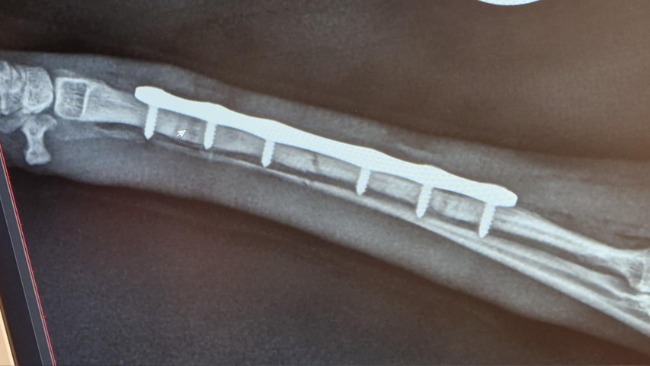

Chanel miała pecha – pierwszy raz złamała łapkę, w wieku 5 miesięcy gdy niefortunnie wylądowała po skoku. Przeszła pierwszą operację, podczas której założono jej tytanową płytkę ze śrubami zespalając złamaną kość promieniową przedniej łapki.

Przez dwa miesiące nie mogła chodzić, ale dzielnie znosiła rekonwalescencję. Niestety, dwa dni po usunięciu implantów doszło do drugiego złamania i kolejnej operacji...